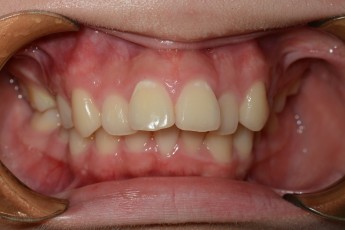

Before

After